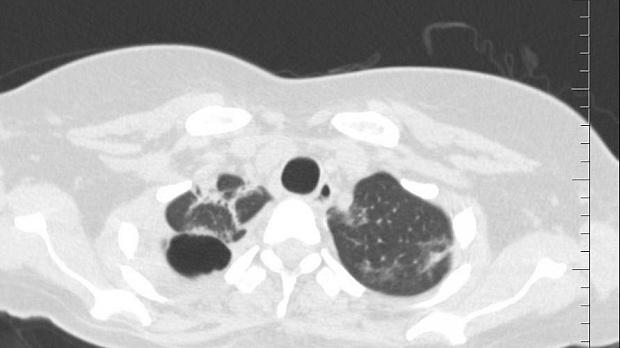

Пациентка переведена к нам в отделение торакальной хирургии из родильного отделения. Будучи беременной на 9 месяце COVID-19 с возникновением двухсторонней вирусно-бактериальной пневмонии с деструкцией в нижней доле правого легкого, эмпиемой плевры и бронхоплевральным свищем. По данным Р-КТ органов грудной клетки: полость деструкции в нижней доле правого легкого. Выполнено дренирование плевральной полости справа. У пациентки – утечка воздуха по дренажу из плевральной полости. 05.06.2020 выполнена клапанная бронхоблокация промежуточного бронха (блокатор Medlung №12) с хорошим клиническим эффектом (сброс воздуха по плевральному дренажу прекратился через 6 часов после вмешательства). Но, через 2 дня пациентка откашляла бронхоблокатор.